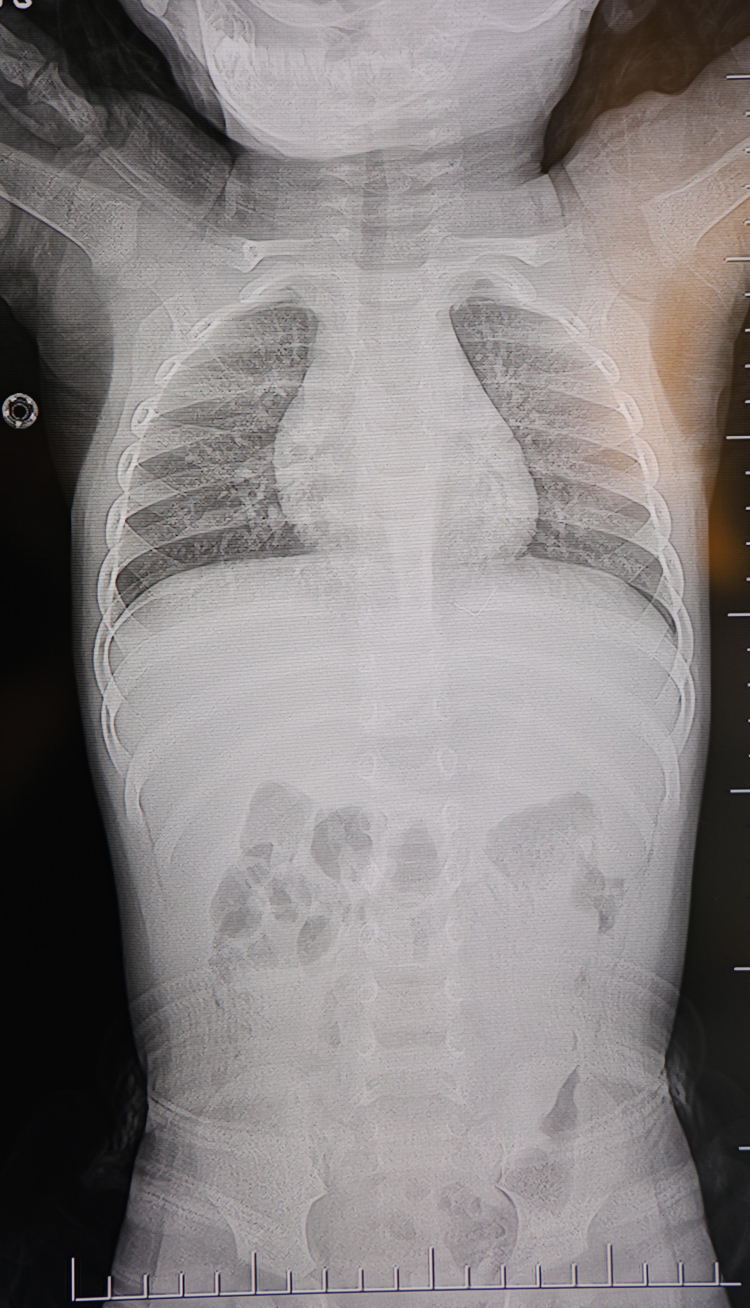

Kahramanmaraş’ta sırt üstü yatmak istemeyen ve yatırıldığında sürekli ağlayan bir yaşındaki bebeğin sırtında, akciğer zarına doğru ilerleyen yaklaşık 2 santimetre uzunluğunda metal bir tel parçası bulundu. Zımba teline benzer tel, gerçekleştirilen başarılı operasyonla çıkarıldı.

HG Hospital Beyin ve Sinir Cerrahisi Uzmanı Prof. Dr. İdris Altun tarafından yapılan muayene ve tetkiklerde, yabancı cismin cilt altında, omurilik kanalına çok yakın ve akciğer zarına doğru ilerleyen bir bölgede olduğu belirlendi. "Yabancı cisim alınmasaydı enfeksiyon gelişebilir, omurilik zedelenebilirdi. Hatta akciğere batarak tümörle karışabilecek ciddi komplikasyonlara neden olabilirdi" diyen Prof. Dr. Altun, ameliyatın detaylarını da paylaştı.

Hasta, genel anestezi uygulanmaksızın, lokal anestezi ve sedasyon altında ameliyata alındı. Başarıyla gerçekleştirilen işlemle, cisim tamamen çıkarıldı. Uzmanlar tarafından yapılan değerlendirmede, çıkarılan parçanın yaklaşık 2 santimetre uzunluğunda, ince zımba teline benzer metal bir tel olduğu tespit edildi.